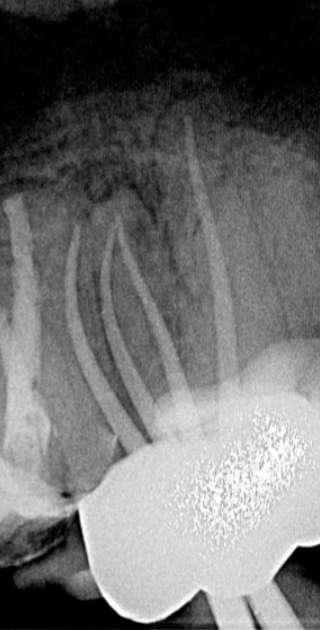

Wenn man sich dieses präoperative Röntgenbild ansieht, sind zwei Hinweise zu diesem endodontischen Fall zu erkennen (Abb. 1): Obliteration der Pulpakammer und enge Kanäle Ungewöhnliche Anatomie der distalen Wurzel

Mit hochtourigen Diamantbohrern wurde eine konventionelle Zugangskavität angelegt und die drei Öffnungen wurden mit Ultraschallspitzen lokalisiert. Die KFeile #08 wurde verwendet, um das endodontische System aller Wurzeln zu erkunden, wobei aber der Apex im distalen Kanal nicht erreicht werden konnte. Das Aufweiten und die Instrumentierung im mittleren Drittel erfolgten mit einer reziprok arbeitenden kleinen (gelben) EdgeOne-Feile (Edge Endo, Albuquerque, NM), die mit Einwärts-Auswärts-Bewegungen von 1-2 mm im Wechsel mit bürstenden Bewegungen zum koronalen Erweitern der Kanäle verwendet wurde. Es wurde eine regelmäßige und reichliche manuelle Spülung mit Lösungen von 5% Natriumhypochlorit durchgeführt. Nach der Aufbereitung des koronalen und mittleren Teils wurde die Arbeitslänge mit der K-Feile #10 bestimmt und das Aufbereitungsverfahren mit martensitischen X7-Instrumenten (Edge Endo, Albuquerque, NM) in den Größen 17 und 25, Konizität .04 abgeschlossen. Die Instrumente wurden mit reziproker Rotation im Uhrzeigersinn (150°-30°) verwendet, um die Torsions- und Biegebelastung zu verringern (Abb. 2).

FALLBERICHT: Abb.1 Abb.2